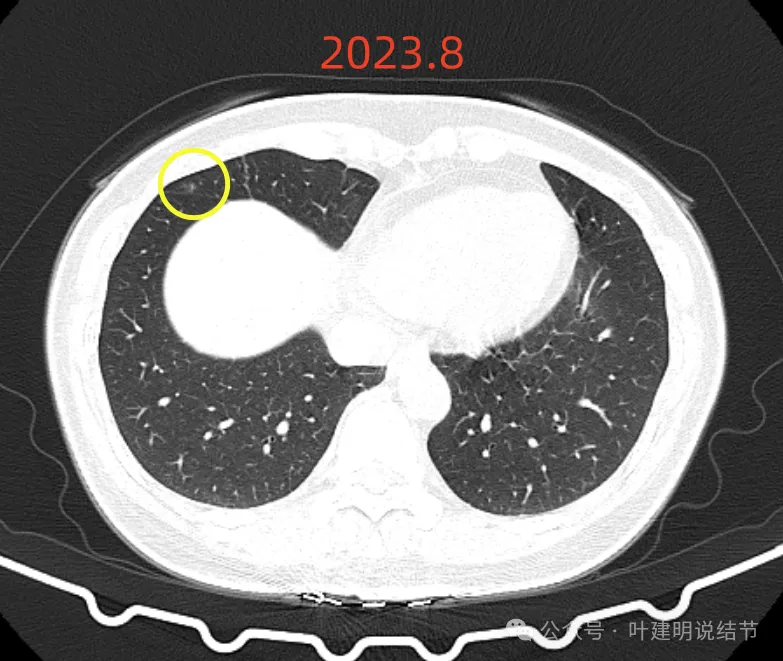

再看2023年8月时复查的影像:

有变化吗?说不上!

点击阅读:问诊分析(2023.9.23):这个于1年多前在国内某著名医院被我叫停手术的肺结节病人,现在怎么样了?